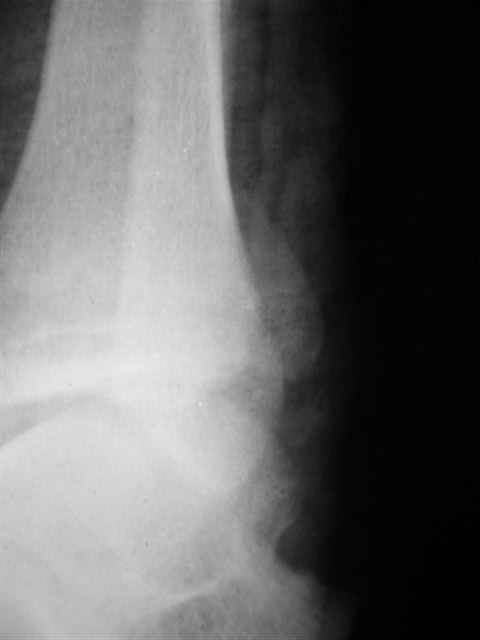

> Если Вас не затруднит, пришлите, пожалуйста, рентгенограммы. Я

> интересуюсь тактикой лечения повреждений голеностопного сустава.

Ничего сверхъестественного, но если есть интерес, то в понедельник пересниму Рг-граммы и отправлю.

Уважаемый Иван,

Я предупреждал, что ничего сверхъестественного. Каюсь, что одна из спиц прошла несколько дальше, чем нужно было, но главное - перелом стабилизирован и больной работает суставом в полном объёме, несмотря на представленную раннее травму коленного сустава.